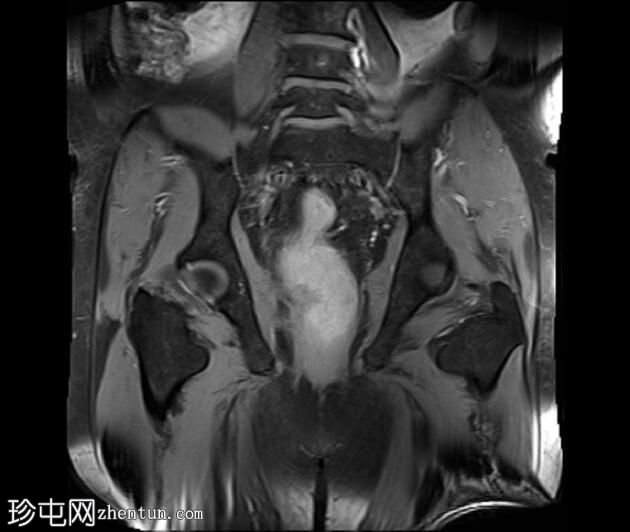

MRI

冠状位

T2加权像

可见一不规则分叶状肿块,累及直肠中段和远端,头尾方向长约7 cm,下缘距肛缘约2.5 cm。在T1加权像和T2加权像上,该病灶相对于骨骼肌均呈高信号。 PDFS(脂肪抑制)图像显示持续高信号强度,提示存在黑色素和/或出血成分。

增强扫描显示病灶内呈不均匀强化。直肠下段7点钟位置的系膜筋膜受累。后方系膜可见少量淋巴结。未见邻近器官侵犯。